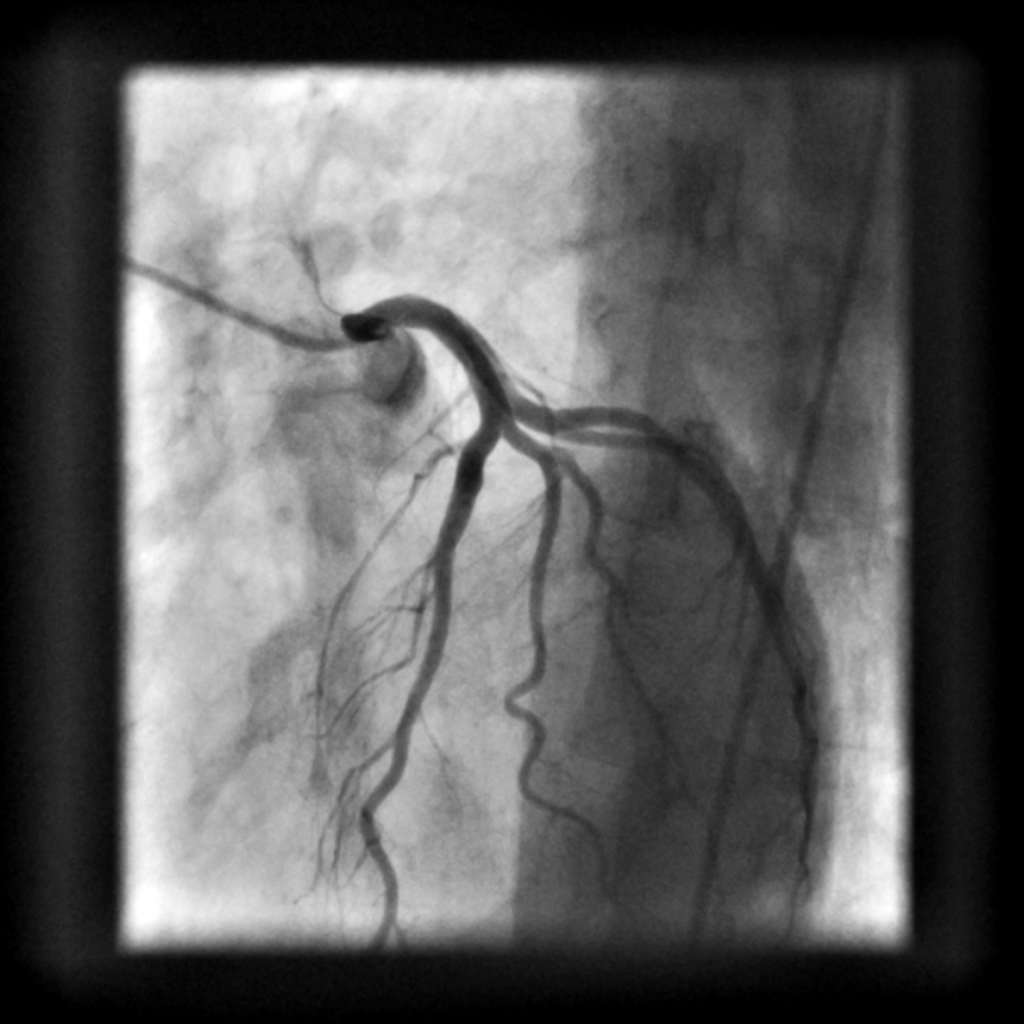

Een serie over ouder worden, littekens en sporen en over hoe de binnenkant van het lichaam zich verhoudt tot de buitenkant.